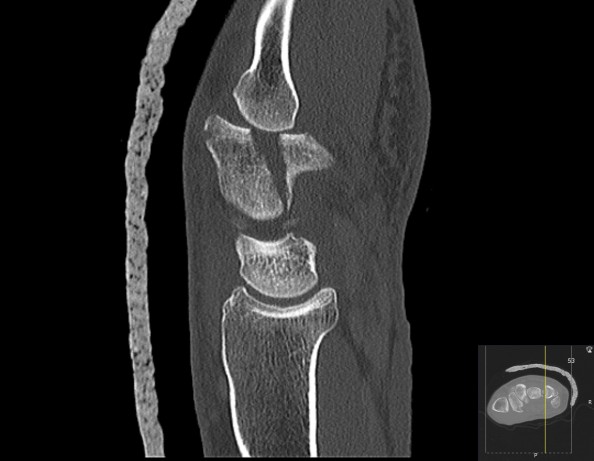

Fraktur i os hamatum

Bildet viser en langsgående fraktur i corpus av os hamatum med subluksasjon av femte karpometakarpalledd hos en mann i 40-årene etter et fall.

Frakturer i os hamatum er sjeldne og utgjør 2–4 % av alle bruddene i håndroten (1). Diagnostikk og behandling er ofte forsinket på grunn av få kliniske funn kombinert med at bruddet kan være vanskelig å oppdage på konvensjonell røntgen. CT er derfor anbefalt ved fortsatt smerte ulnart i håndroten etter negativ røntgenundersøkelse (1, 2). Bruddene deles inn i fraktur i corpus og hamulus. Skaden er forårsaket av aksial kompresjon av os hamatum gjennom fjerde og femte metakarp, som begge artikulerer med os hamatum. Dette kan resultere i en subluksasjon i karpometakarpalledd fire og fem med en koronal bruddlinje gjennom os hamatum, oftest i dorsale del. Fjerde og femte karpometakarpalledd tillater cirka 30° bevegelse, og er viktig for gripekraften. Det er derfor viktig med tilheling uten trinndannelse av bruddet og uten subluksasjon i karpometakarpalleddet for å redusere risikoen for artroseutvikling. Isolerte, udislokerte frakturer i corpus vurderes oftest som stabile og kan behandles med gipsing, mens dislokerte frakturer anbefales reponert og fiksert med pinner, alternativt plater eller skruer, med samtidig reposisjon og fiksasjon av det sublukserte karpometakarpalleddet.

Prognosen er god ved adekvat behandling. Den vanligste senfølgen er smerter etter tung belastning (2), som kan skyldes artroseutvikling, noe som alltid er en risiko etter en intraartikulær fraktur. Denne pasienten ble først operert med lukket reponering og pinnefiksasjon. Frakturen tilhelet, men pasienten utviklet posttraumatisk artrose i både fjerde og femte karpometakarpalledd, og ble ett år etter skaden operert med avstivning av fjerde og femte karpometakarpalledd med platefiksasjon.